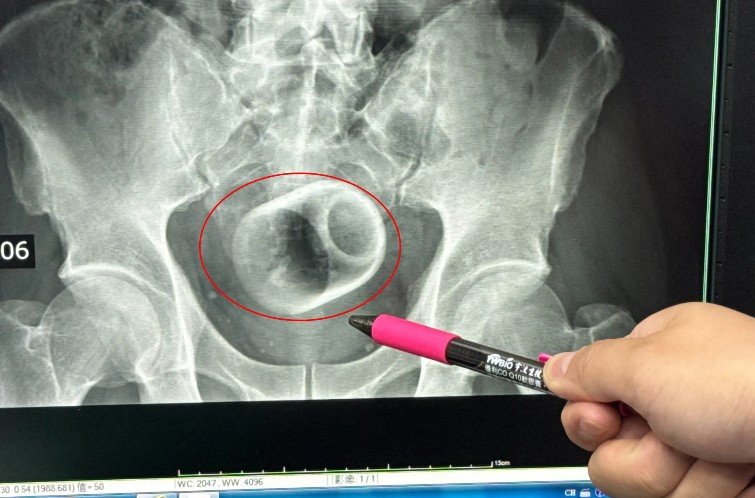

엑스레이 촬영 결과 컵은 A씨의 대장에 완전히 끼어 있었으며 장 일부는 괴사 상태였다. 그는 엄청난 복통과 복부 팽만감을 호소했고 즉시 수술실로 이송됐다.

수술을 맡은 우쿤다 박사는 긴 도구를 사용해 컵을 빼내려고 했지만 컵이 미끄러워 여러 번 실패했다. 결국 우쿤다 박사는 A씨를 전신 마취하고 장을 절개한 뒤 컵을 제거했다.